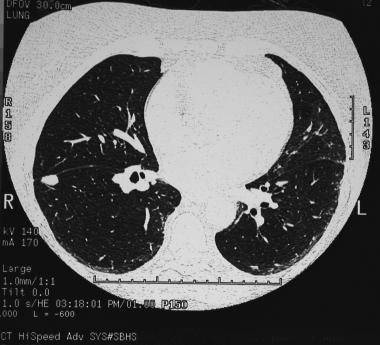

КТ легких: показания

Томографию легких для первичной постановки диагноза назначают, если у пациента наблюдается:

- длительный кашель, в том числе с кровью и нетипичным отделяемым;

- непрекращающаяся лихорадка, постоянно повышенная температура тела;

- головные, мышечные боли невыясненного происхождения;

- синюшность губ, кожных покровов;

- общая слабость, быстрая утомляемость;

- боли в груди ноющего и острого характера.

Велика диагностическая ценность КТ при оценке эффективности противоопухолевой терапии. Практически моментальное получение результатов обследования позволяет быстро скорректировать тактику лечения.

В каком случае еще назначают КТ легких? Диагностика может быть показана при травмах грудной области, в том числе сопровождающихся пневмотораксом (разрывом легочной ткани), кровотечениями, при выявлении на рентгенографии патологических очагов, свидетельствующих о пневмонии, эмфиземе, абсцессах, при увеличении внутригрудных лимфоузлов.

Суть исследования

Томография является высокоинформативным методом послойного исследования тканей и внутренних органов, позволяющим увидеть на снимке даже самые мелкие детали – хорошо визуализируются очаги размером в 1–2 мм. Она относится к рентгенологическим исследованиям, когда изображение формируется путем просвечивания каждого среза, толщина и направление которого может регулироваться, исходя из характера легочной патологии.

Проходя сквозь ткани различной плотности, излучение ослабевает, а степень его изменения регистрируется чувствительными сенсорами. Полученная информация анализируется компьютером и нередко представляется в виде трехмерной картинки. Томографическое исследование легких может выполняться в нескольких режимах:

- Непрерывный – делают все срезы органа.

- Дискретная – интервал между срезами увеличен.

- Прицельная – анализируют лишь определенный участок органа.

Сравнивая КТ легких при пневмонии с обычным рентгенологическим исследованием, преимущества томографии очевидны: более высокая чувствительность и точность. Она позволяет обнаружить наиболее мелкие детали патологического процесса, не давая усомниться в диагнозе. Однако исследование не так доступно и сопряжено с более существенной лучевой нагрузкой на пациента.